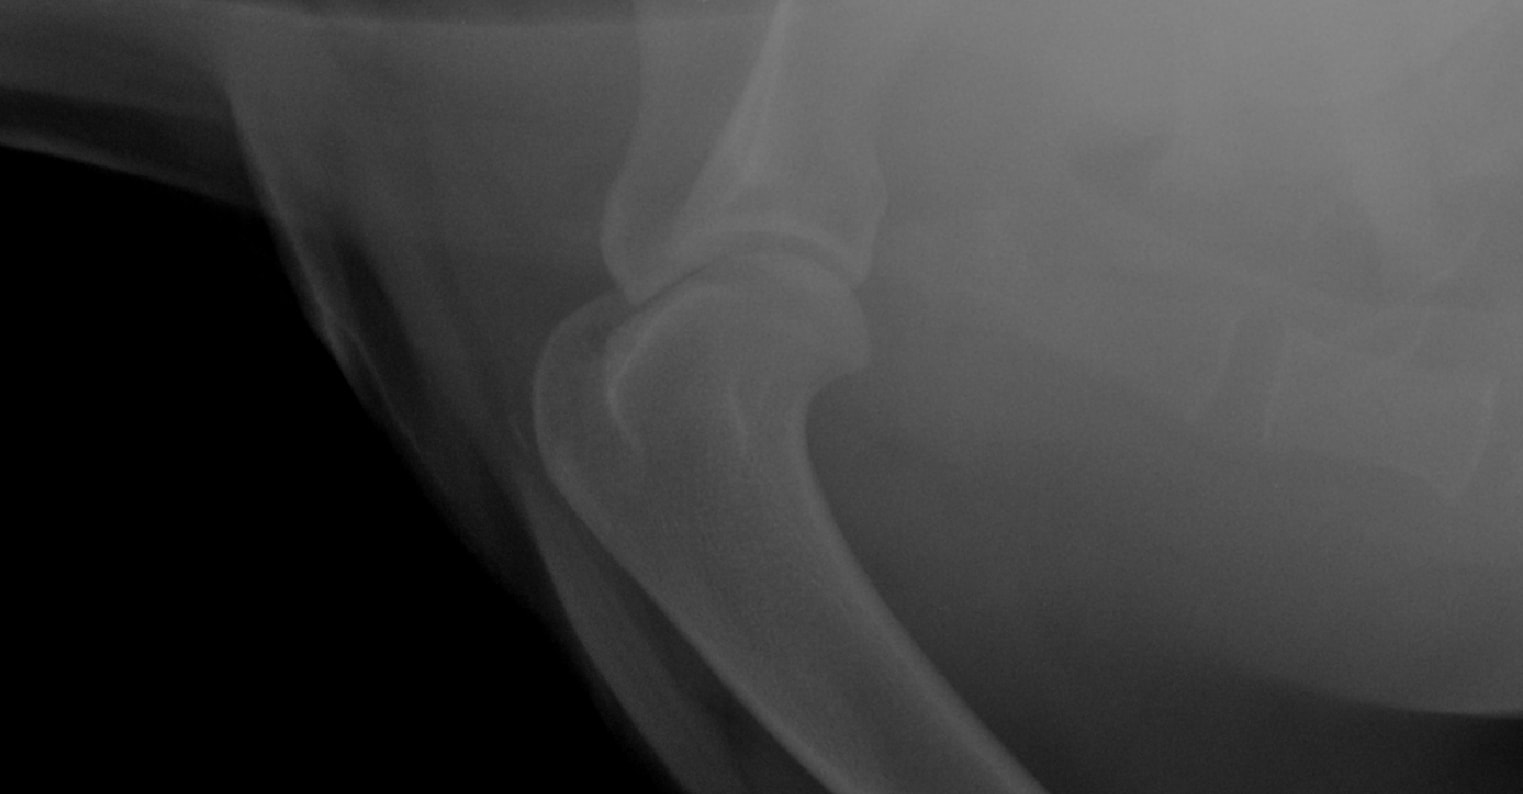

Pet's info: Dog | Rottweiler | Male | neutered | 4 years and 5 months old | 110 lbs

Hi, I recently asked a question on here regarding my dog. we took him for a 2nd opinion regarding his right front leg. they too cannot see what is wrong - the vet suspects bone cancer or broken cartridge in his humorous. All they did was give us anti inflams for 4 weeks and said come back for more xtrays. My question. if it is bone cancer - then Why are they making us wait for it to progress. I have attached the Xrays again. Why have they not done a bone biopsy? this is our 2nd opinion already

I don't see any abnormalities in the radiographs that you show. Bone cancer can occasionally be difficult to diagnose before it is very severe. To biopsy a bone for possible cancer, you need to know where in the bone to sample, so it is not as simple as just picking any part you want. Advanced diagnostics like MRI or CT may be more helpful at looking more closely at the soft tissue (muscles, tendons, ligaments) and bone to see if there are any abnormalities. You will likely need a referral to a specialty hospital for this procedure. If you are concerned about something life-threatening like bone cancer, I would recommend that you speak with either vet about a referral.